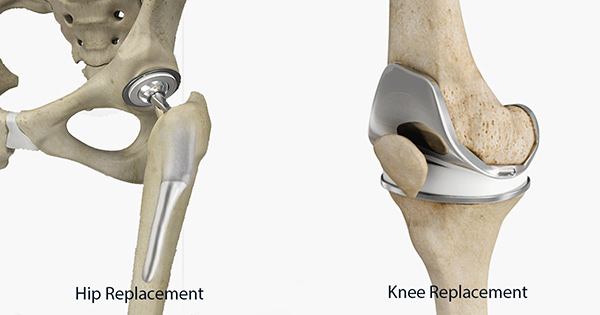

В Україні функціонує Електронна система забезпечення формування та ведення електронної черги на безоплатне ендопротезування. Запровадження електронної черги – це важливий крок до забезпечення прозорості, ефективності та доступності медичної допомоги пацієнтам із тяжкими захворюваннями, травмами та яким необхідне часткове або повне ендопротезування кульшового, колінного, плечового чи ліктьового суглоба.

У 2025 році в заклади охорони здоров’я буде поставлено понад 23 тисячі ендопротезів, які придбані ДП «Медичні закупівлі України» на замовлення Міністерства охорони здоровʼя України коштом держбюджету. Серед них: ендопротези колінного суглоба, кульшові суглоби цементні, ендопротези кульшового суглоба ревізійні, імпланти та інструменти для корекції складних сколіотичних деформацій хребта тощо.

Наразі в черзі на ендопротезування понад 19 тисяч (19 798) пацієнтів, найбільше – у медзакладах м. Києва. Найпоширеніша потреба — первинне ендопротезування колінного суглоба, в черзі на цю операцію знаходиться понад 10 тисяч пацієнтів. У більшості медзакладів в черзі знаходиться від 50 до 100 пацієнтів.

Загальна статистика черги станом на 19 червня 2025 року (по типам протезів):

- Ендопротез колінного суглоба – 10525

- Ендопротез тотальний кульшового суглоба (безцементний) – 6617

- Ендопротез кульшових суглобів цементний (тотальний ендопротез) – 2341

- Ендопротез кульшових суглобів цементний: ендопротез однополюсний з подвійною сферою обертання – 26

- Ендопротез колінного суглоба (ревізійний зв’язаний ротаційний) – 147

- Ендопротез кульшового суглоба (ревізійний) – 142